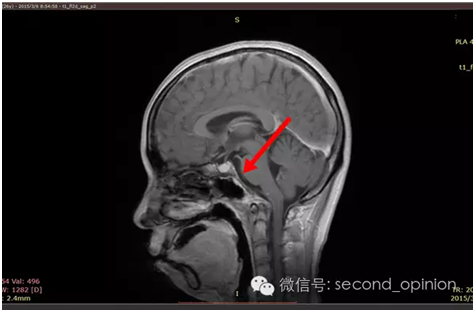

2014年9月1日MRI(手术治疗前)